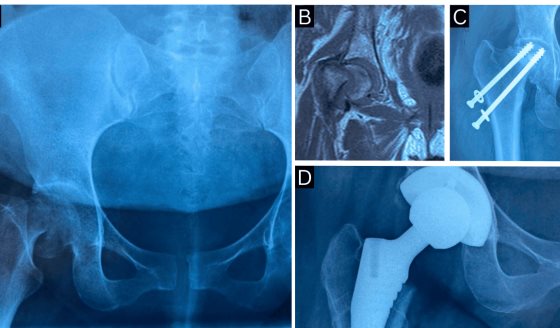

Primigesta presenta necrosis avascular bilateral de cadera con fractura subcapital por trabajo de parto